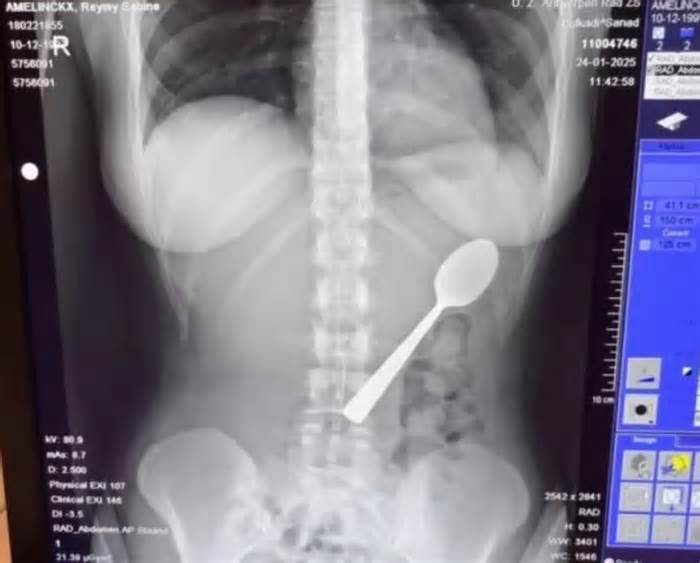

Một phụ nữ Bỉ vô tình nuốt trọn chiếc thìa dài 17 cm sau khi chó cưng bất ngờ nhảy lên người lúc cô đang ăn sữa chua.